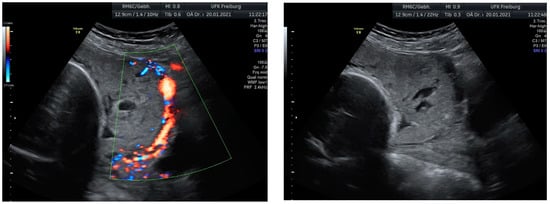

Sonographic findings (Figure 4):

Figure 4.

shows suspected placenta increta with dehiscence in the area of scar tissue from the previous uterotomy.